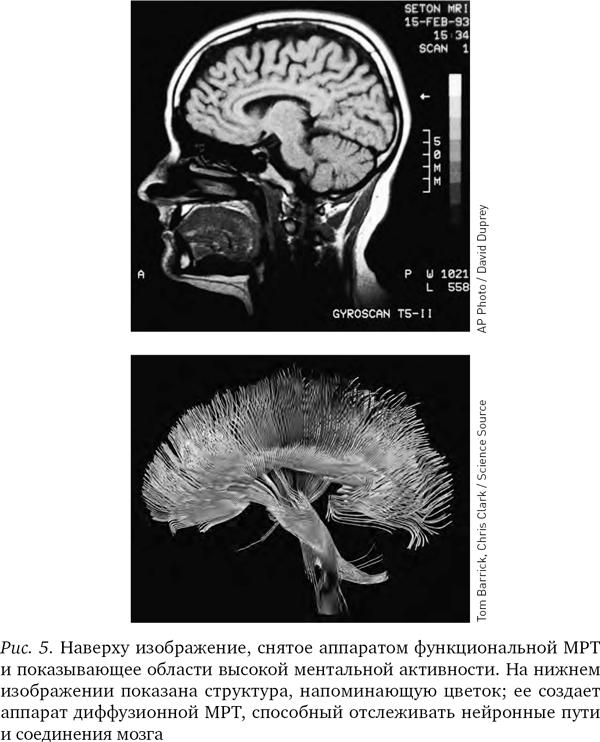

Подобно изобретению телескопа, появление в середине 1990–2000-х гг. аппаратов МРТ и еще нескольких методов сканирования мозга полностью преобразило нейробиологию. За те же 15 лет мы и о мозге узнали больше, чем за все наше существование, и разум, прежде считавшийся непознаваемым, наконец выходит на авансцену.

Это описание мозга примерно отражает состояние науки в 1980-е гг. Однако в 1990-е гг., когда развитие физики привело к появлению новых технологий, механизмы мышления стали изучаться в мельчайших подробностях, а нейробиологию ожидал бум научных открытий. Одной из рабочих лошадок, обеспечивших успех этой революции, стал аппарат МРТ.

Вначале, когда аппараты МРТ только появились, они могли показывать структуру мозга лишь в статике и на различных его участках. Однако в середине 1990-х гг. был изобретен новый вид МРТ, получивший название функциональной магниторезонансной томографии, или фМРТ; и теперь аппараты уже различали присутствие кислорода в крови в сосудах мозга. (Иногда ученые обозначают маленькой буквой перед аббревиатурой МРТ тип аппарата, но мы будем использовать аббревиатуру МРТ во всех случаях.) На полученных при помощи МРТ изображениях не виден непосредственно ток электричества в нейронах, но поскольку без кислорода нейроны не получат энергии, насыщенная кислородом кровь косвенно указывает на поток электрической энергии в нейронах и наглядно показывает, как различные области мозга взаимодействуют между собой.

Различные химические элементы реагируют на разные частоты радиоволн по-разному, поэтому мы можем, изменяя частоту волны, определять, где какие элементы находятся. Как уже отмечалось, при фМРТ в основном отслеживаются атомы кислорода в крови и измеряют кровоток, но вообще-то аппарат МРТ можно настроить на любое вещество. В последнее десятилетие появилась новая разновидность МРТ — диффузионно-тензорная; она отслеживает движение воды в объеме мозга. Вода в мозге следует по нейронным путям, поэтому диффузионно-тензорная томография позволяет получить красивые картинки, напоминающие переплетение растущих в саду лиан. Теперь ученые могут мгновенно определить, как части мозга связаны между собой.